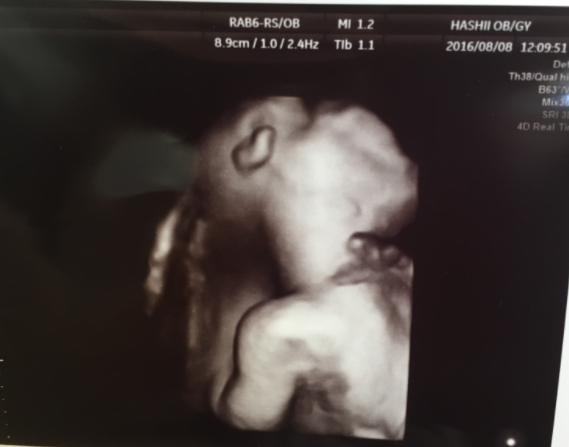

26週3日(26w3d・男の子)|まゆゆーん さん(26歳)

エコー写真撮影時のエピソード:

はじめての赤ちゃんはパパ待望の男の子!どんな子がお腹の中に入ってるかなと楽しみで待ち遠しかった4Dエコー!26w3dにパパと一緒に病院に行きました。

パパは寝る時に手をグーにして顔の前に置いて寝るのがくせ。 なんと赤ちゃんも同じポーズでびっくり!そっくり顔にポーズまで同じで生まれる前から本当にそっくりでした^_^

パパは驚きと感動で涙が出たみたい^_^一生忘れない思い出の一枚です!